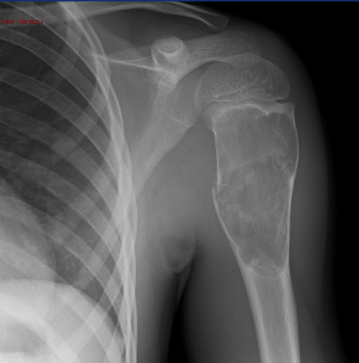

Most common area for Osteochondroma?

-Knee and the humerus

-Adjacent to growth plates and pointing away from articulations

Imaging Features of Osteochondroma

-Corticomedullary continuity

-Pedunculated (thin stalk with large distal cap that is covered in hyaline cartilage)

-Sessile (Broad based osseous excrescence with possible overlying cartilaginous cap)

-Potential sign of accommodation of adjacent osseous structures or signs of soft tissue irritation

Sessile Osteochondroma on X-ray

Sessile Osteochondroma in Knee on X-ray

Hereditary Multiple Exostoses

-AKA osteochondromatosis

-Multiple osteochondromas that may cause severe boney deformity

-80% discovered by 10 years of age

Distribution of Hereditary Multiple Exostoses

-Knee

-Ankle

-Shoulder

-Hip

-Wrist (madelung-like deformity)

HME on X-ray